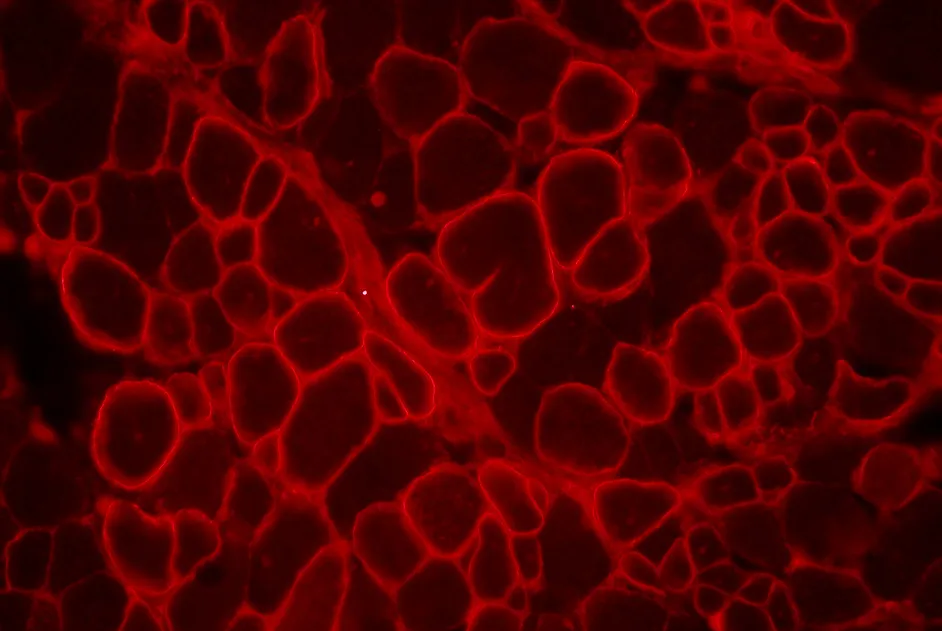

Généthon a étudié les interactions entre des protéines des myopathies des ceintures et d’autres protéines de l’organisme. Ces liens forment un réseau dense appelé Interactome.